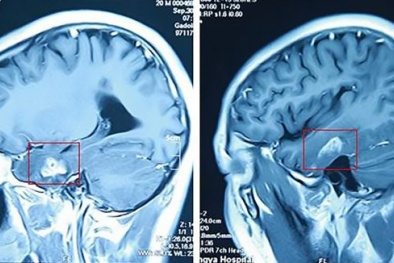

Con sán dài 11 cm sống trong não nam thanh niên sau 1 lần đứt tay

(VietQ.vn) - Trang Metro đưa tin, một thanh niên 19 tuổi có tên Wen Xiaoli có một con sán dài 11 cm sống trong não mà không hề hay biết.